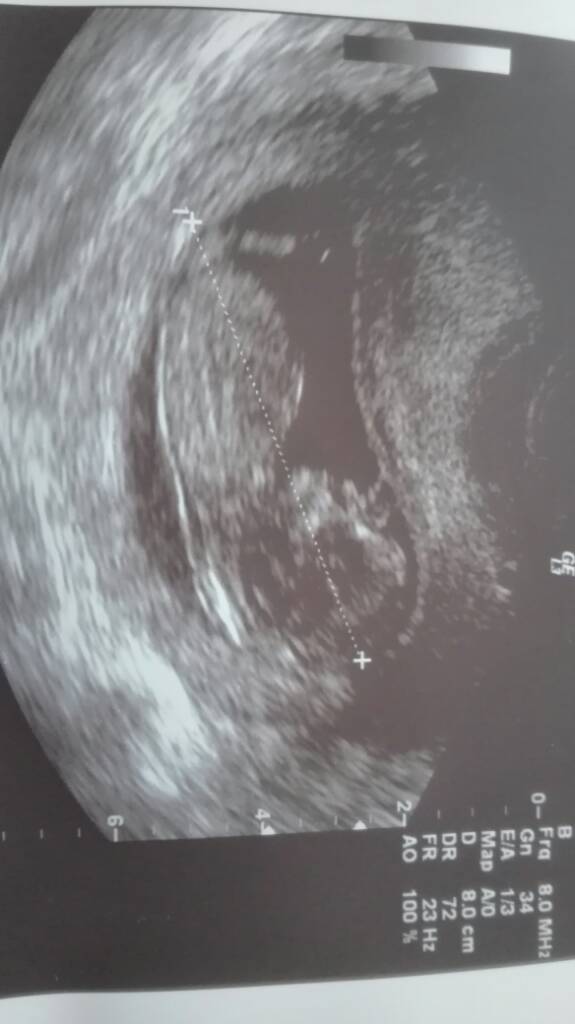

Ja miałam też krwiaczka i musiałam leżeć plackiem 2 tygodnie, ale nie wyobrażam sobie pracować, 8h na nogach i z taką ilością pacjentów jaka jest u nas.